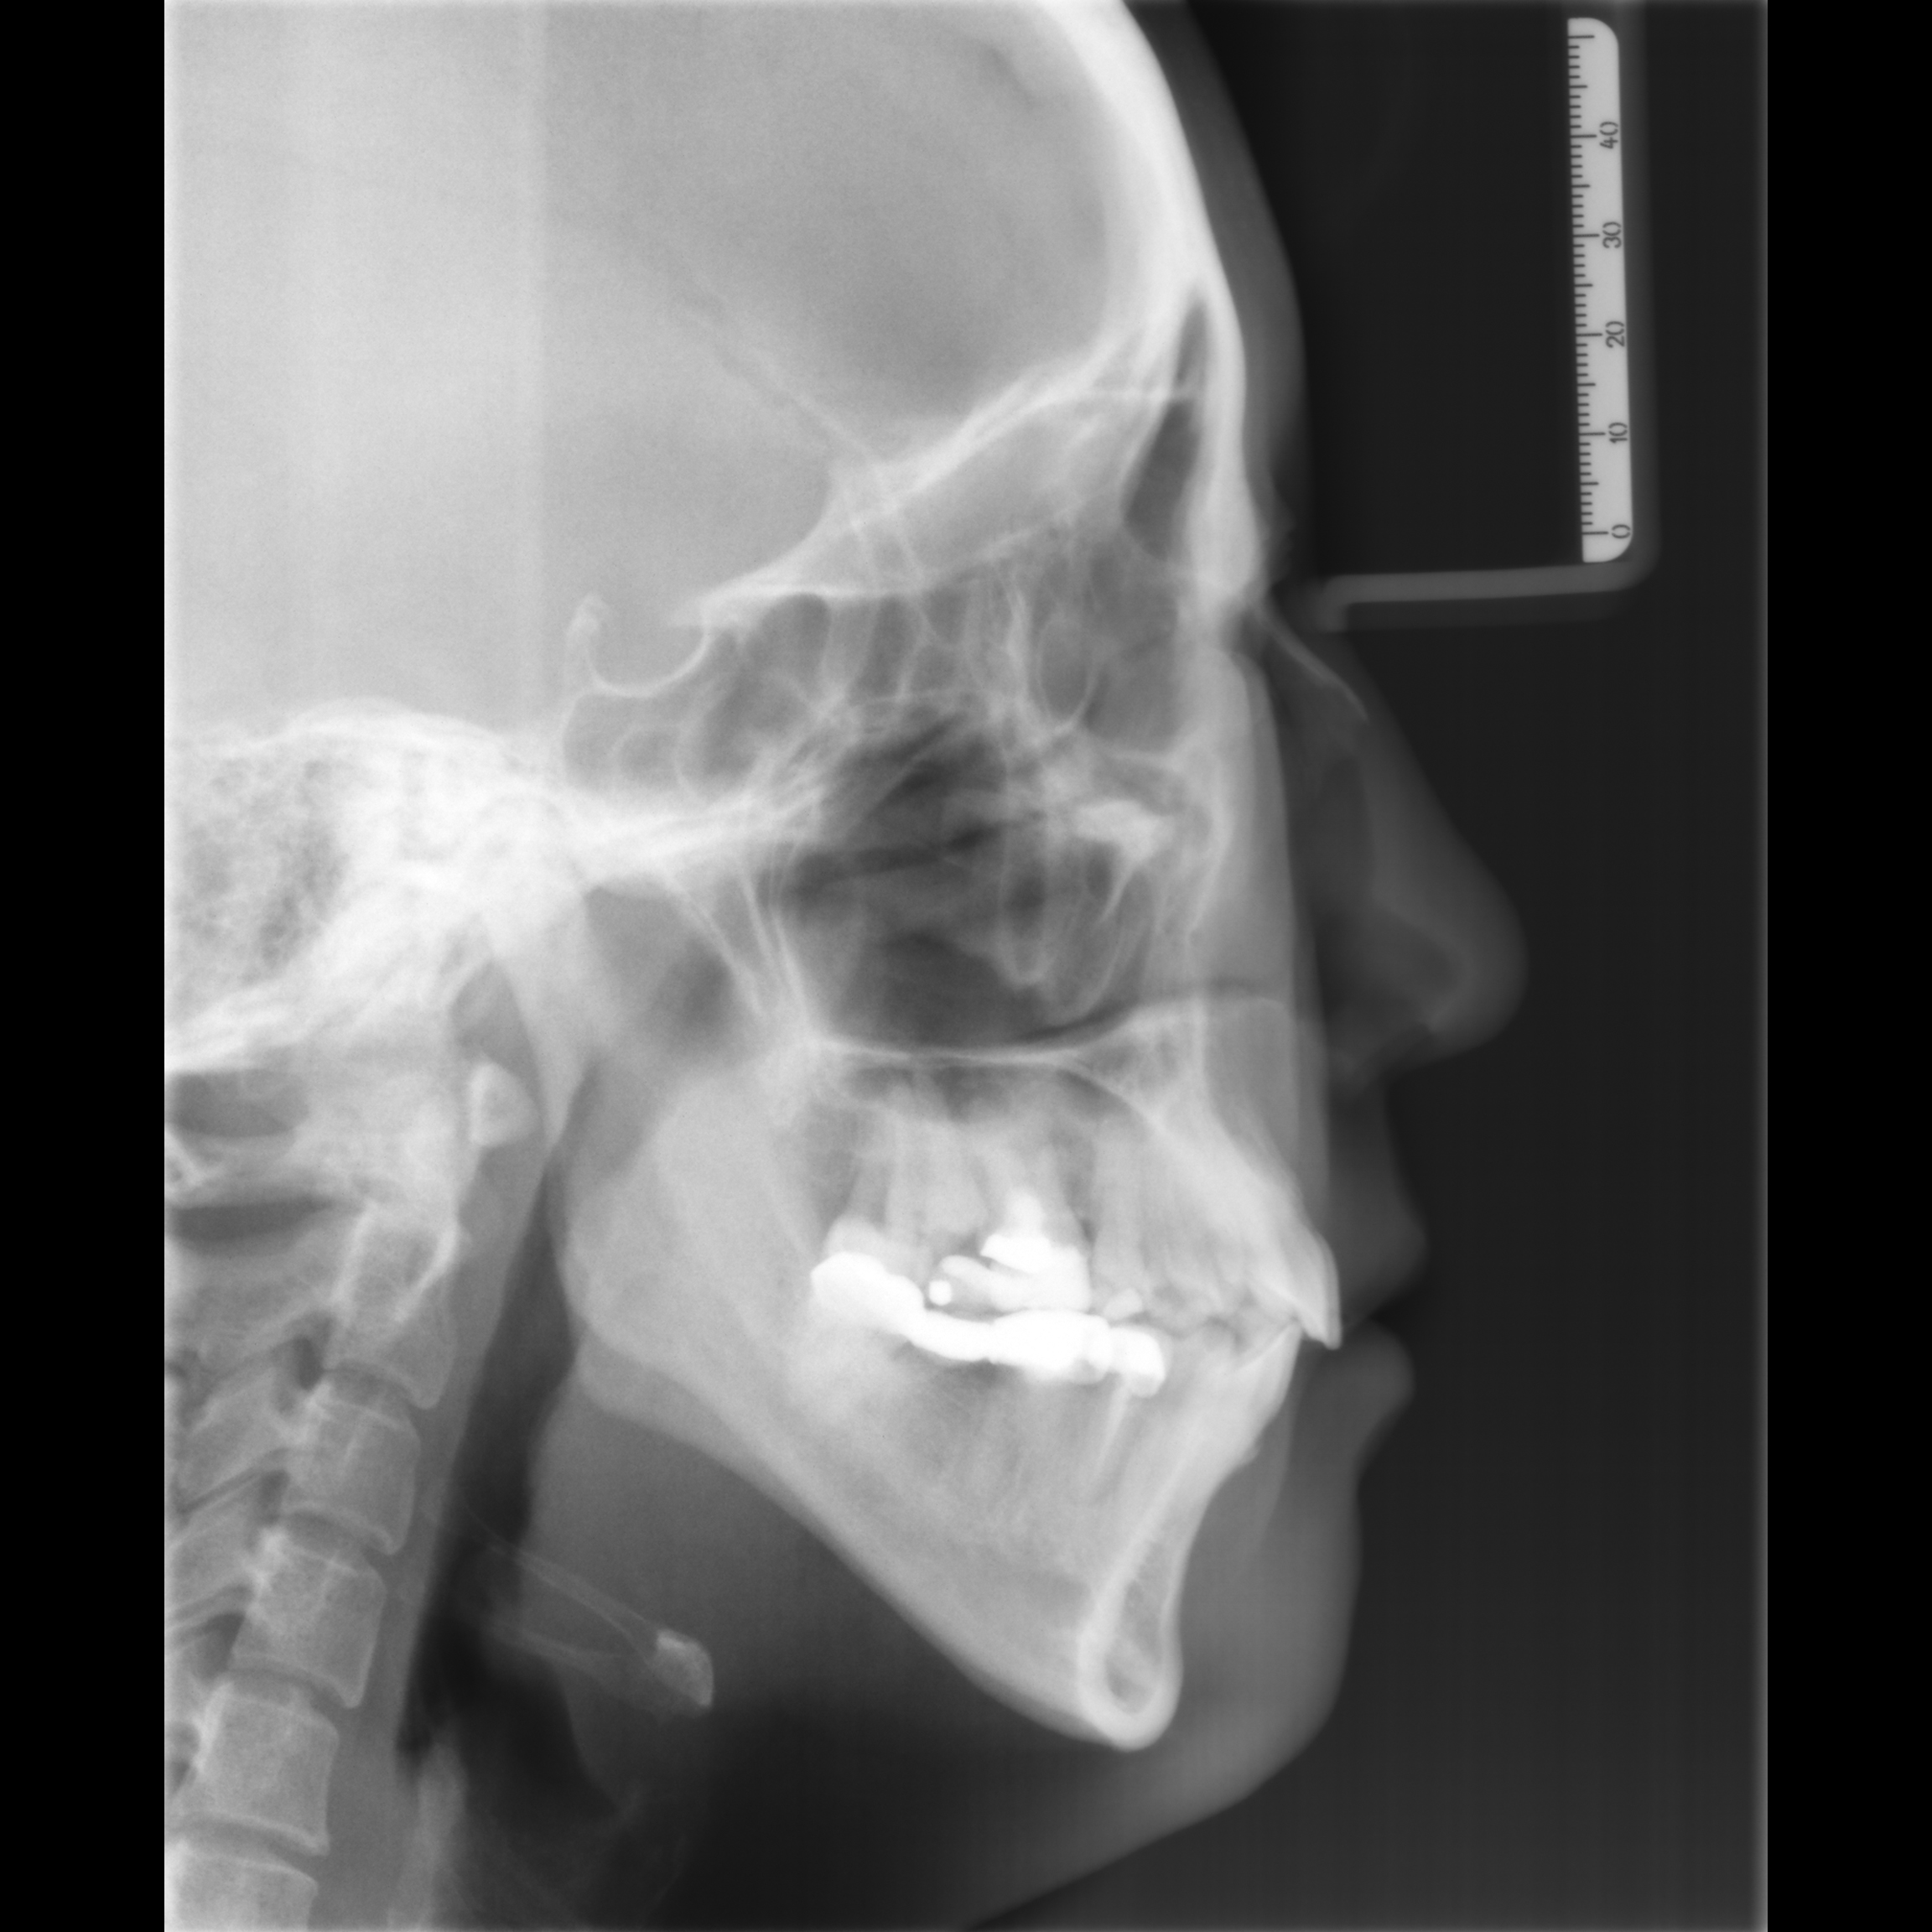

Lateral cephalogram and orthopantomogram (OPG) radiographs are routinely taken for each orthodontic patient for diagnostic and treatment planning purpose. Compared with panoramic radiograph, lateral cephalogram contains the entire craniofacial bones and soft tissue. Because of the way the lateral cephalogram were taken, the left and right craniofacial bones and teeth overlapped together, so the lateral cephalogram can provide more information than panoramic radiograph. However, no one has done any research to infer age and gender based on deep learning of lateral cephalogram.

Because the lateral cephalogram contains the cervical spine, all teeth and craniofacial bones, as well as the craniofacial soft tissue. Therefore, it can simultaneously reflect the aging changes of these areas. So far, the study of age estimation using lateral radiographs is still a blank, so we choose lateral radiographs as the research object.